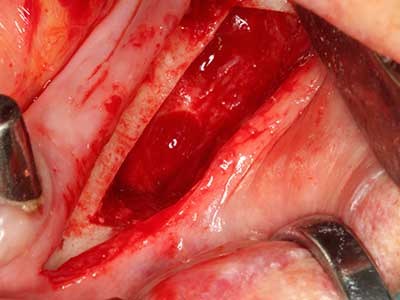

Фиг. 1: Препарация на костно покритие с Piezomed (W&H Залцбург, Австрия).

Фиг. 6: След препарация на мукопериосталната клапа.